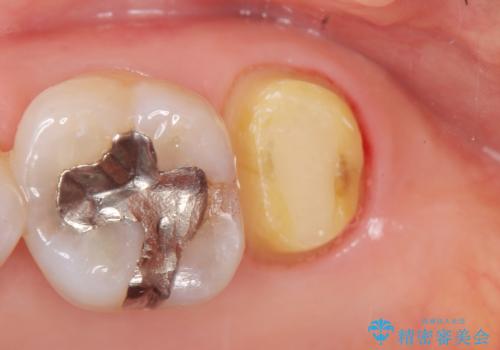

クラウンの将来的な虫歯の再発を防ぐために周囲の歯ぐきを切除することで歯の高さを出し安定した歯周環境にしたのち噛み心地の良いゴールドクラウンを製作します。

クラウンを装着した歯の虫歯の再発を防ぎ長い予後を期待するために削った箇所をしっかりとかぶせる適合の良さが必要はもちろんですが、セメントの漏洩を防ぐためにクラウンの十分な支台高径を歯周外科を行い獲得しました。